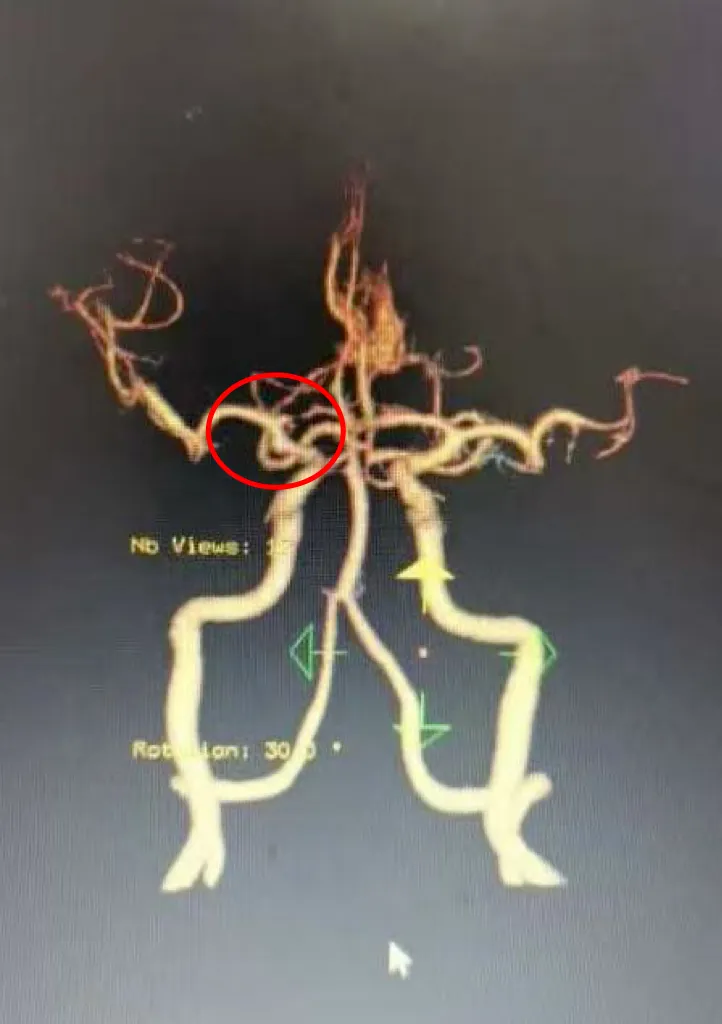

术前头部CTA

患者张某某,女,58岁,因突发头痛头晕1小时入院。入院时神志昏睡,精神差,双侧瞳孔等大等圆,对光反射消失,颈部抵抗,四肢肌力检查不配合等。急查头部CT平扫,提示自发性蛛网膜下腔出血,右侧额颞叶硬膜下血肿,右侧颞叶脑内血肿。患者病情十分危重,紧急收住医院神经外科,予对症治疗后,患者病情逐渐好转,神志清醒。经完善头部CTA提示,右侧颈内动脉后交通动脉瘤并破裂出血,诊断为颅内动脉瘤破裂出血,建议其尽快进行手术治疗,开颅夹闭动脉瘤是颅内动脉瘤治疗的重要方式,安全性高,恢复快、预后佳。